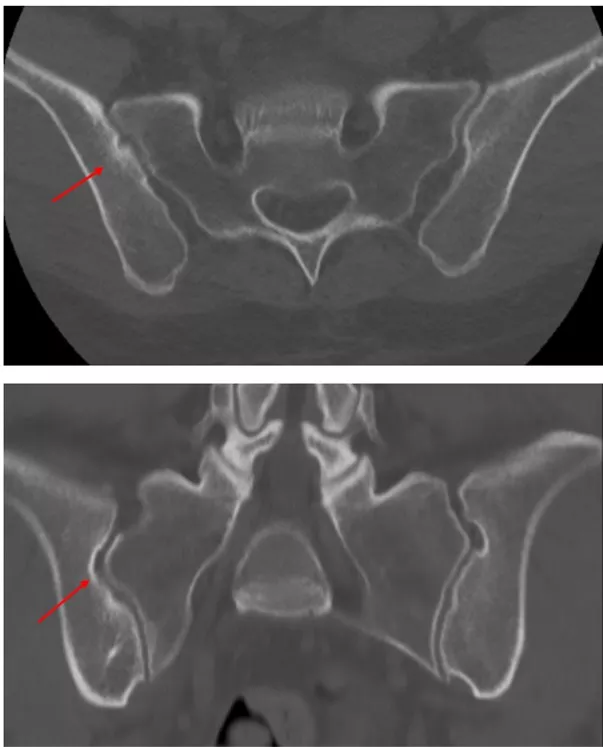

一方、下位胸椎-腰椎MRIではT2 STIR画像でL5とS1の椎体に骨髄浮腫を認め、その他の椎体辺縁にもT2延長病変を認めた(写真5)。

典型的な炎症性背部痛の病歴を有していたこと、MRIで仙腸関節に活動性炎症所見はないがCTで以前の炎症を示唆する所見が示唆されたことなどから、総合的にX線基準を満たさない体軸性脊椎関節炎と診断した。NSAIDs内服は無効であったため、生物学的製剤による治療を開始した。

写真5 下位胸椎-腰椎MRI